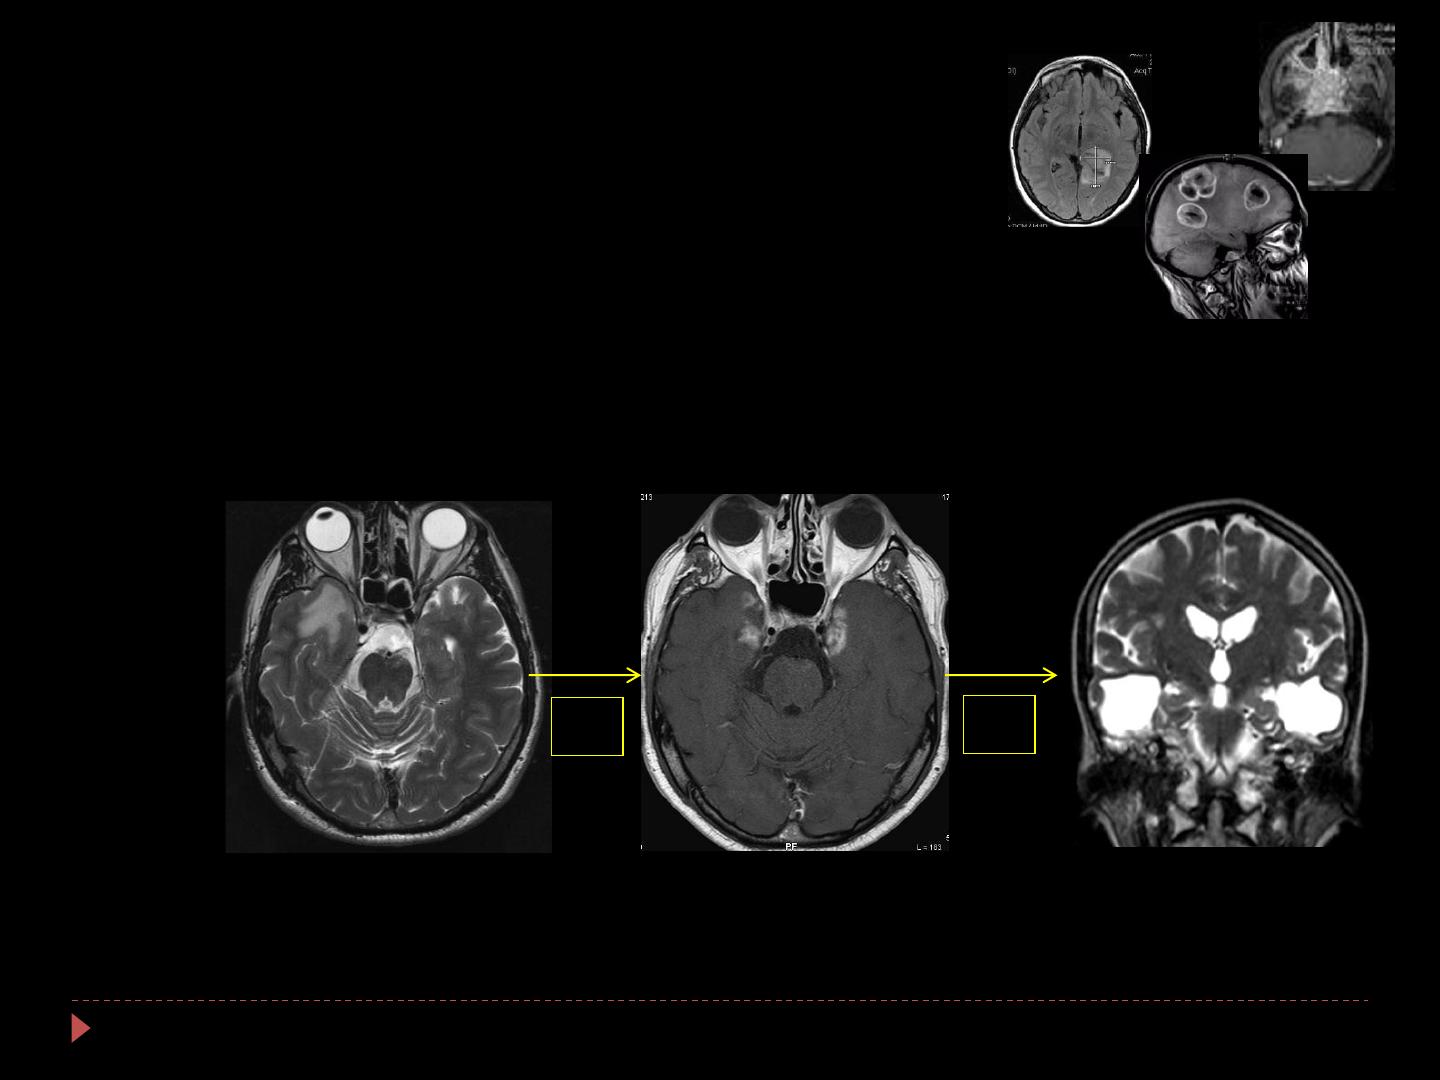

Radionécrose focale

1 / 24 100%